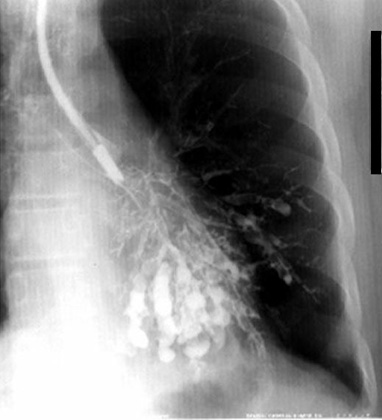

Bronchogram

Saccular Bronchiectasis left lower lobe. Bronchograms are rarely done nowadays.